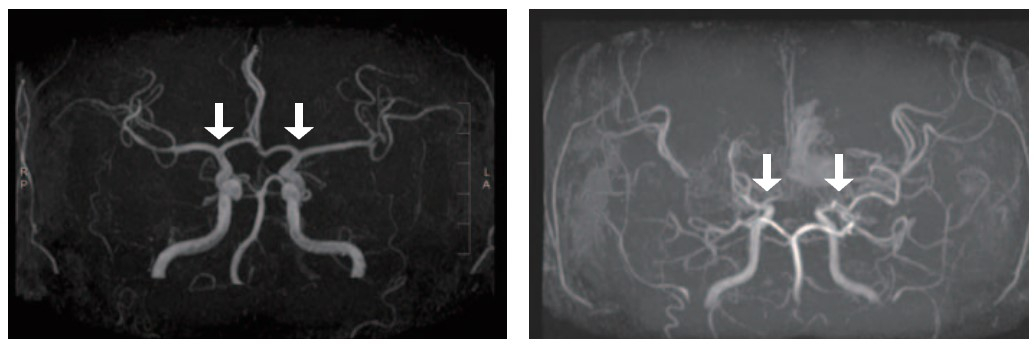

모야모야병은 특별한 원인 없이 대뇌에 혈액을 공급하는 내경동맥의 가지치는 부위 혈관이 서서히 좁아지는 만성 진행성 뇌혈관질환이다. 이로 인해 혈류가 부족해지고, 부족한 혈류를 보충하려는 비정상적인 미세혈관들이 자라나지만, 이 혈관들은 혈액을 충분히 공급하지 못하고 터지기 쉬워 뇌경색·뇌출혈과 같은 심각한 소아 뇌졸중을 유발한다.

지금까지 모야모야병을 확진하려면 침습적인 뇌혈관 조영술이 표준적인 검사였고, 이는 특히 소아에게 큰 부담을 주었다. MRI/A와 같은 비침습적 검사도 있지만, 혈관 협착이 과장되게 나타나는 경우가 있고 뇌기저부의 모야모야혈관을 자세히 평가하기 어려워 조기 진단과 질병의 진행 상태를 정밀하게 파악하는 데 한계가 있었다. 이에 따라 액체 생검(혈액 등 체액을 통한 진단)의 필요성이 꾸준히 제기되어 왔다.